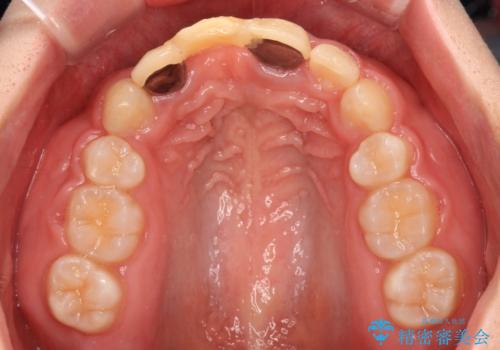

- 矯正治療中に装着していた仮歯を綺麗にしたいとのことで来院された患者様です。

小学生の頃に歯をぶつけて抜歯となりブリッジを装着したそうですが、その後矯正治療を行うに当たりブリッジを切断したとのことでした。

残っている歯根の状態はあまり良くなく、長期的な予後を考えると抜歯を検討するべきでしたが、20代前半という年齢を考え、オールセラミックブリッジにて補綴治療を行うこととしました。